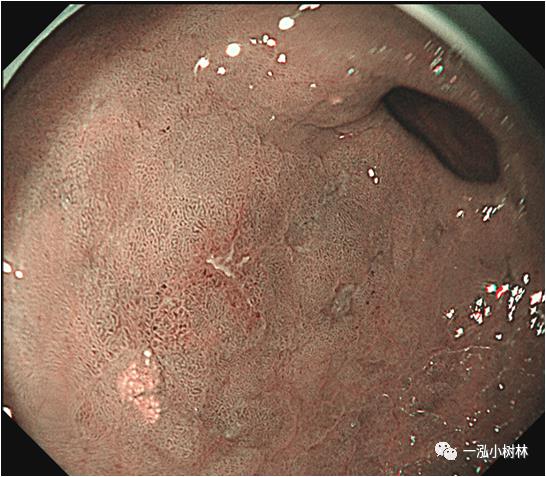

例1 胃窦病变

图1a 白光内镜:胃窦小弯可见IIa+IIc病变,范围2.0cmx1.5cm,微发黄,似胃炎样外观,边界线可疑。